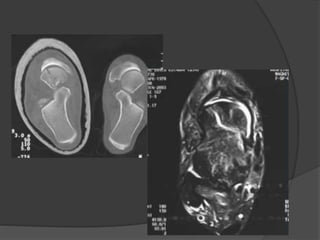

Evaluación imagenológica

 Rx anteroposterior, mortaja y lateral de tobillo

 Rx anteroposterior, lateral y oblicua de pie

 Rx proyección de Canale

 TAC

 RMN

 Gammagrafía